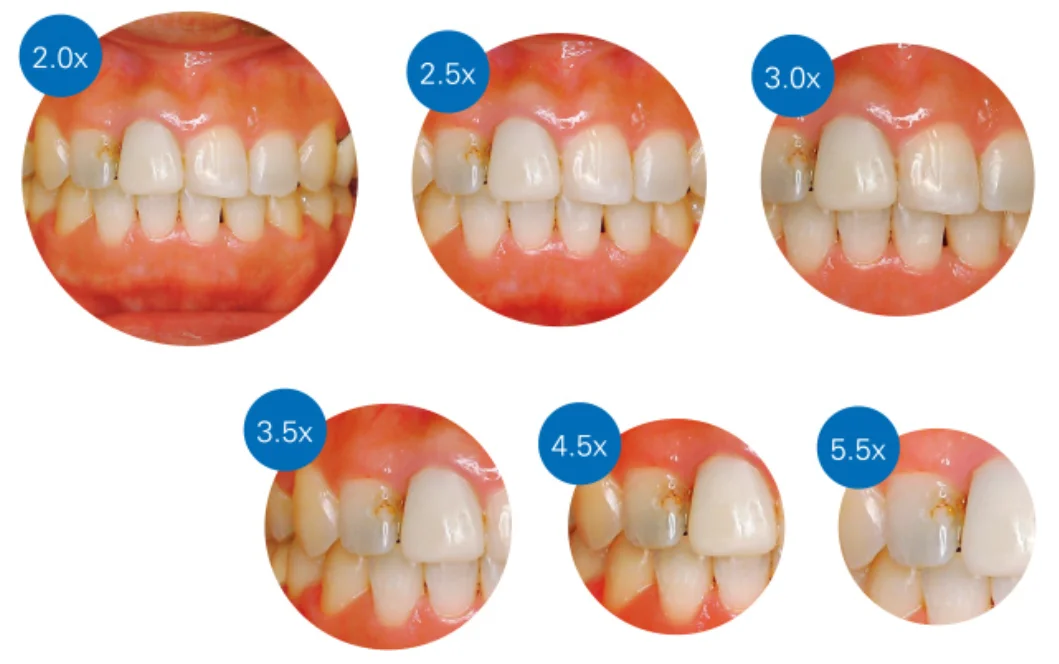

マイクロテック:エルゴTTLルーペレビュー。【歯科医師・歯科衛生士向け】

こんにちは。 今回は完全に歯科医師・歯科衛生士向けの記事になります。 表題の通り、今回はマイクロテックさんが販売しているエルゴTTLルーペのレビューを行っていきます。 公式サイトは こちら 。 さて。こちらは国内での流通開始が6月からで、空…

続きを読む →